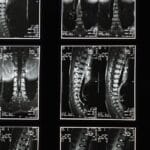

Une hernie discale se produit lorsque le noyau gélatineux du disque intervertébral se déplace, provoquant une pression sur les nerfs environnants. Cette condition se manifeste généralement par des douleurs, des engourdissements ou des faiblesses musculaires. Les hernies discales peuvent être classées comme cervicales, lorsqu’elles affectent la région du cou, ou lombaires, lorsqu’elles touchent le bas du dos.

Une hernie discale se produit lorsque le noyau gélatineux d’un disque intervertébral dépasse et comprime les nerfs environnants. Cela peut causer des douleurs, de la faiblesse musculaire, ou des fourmillements dans les membres. Les hernies discales peuvent survenir dans la région lombaire, affectant le bas du dos, ou dans la région cervicale, impactant le cou. Chaque type demande une attention particulière pour ne pas exacerber les symptômes.

La hernie discale est une affection de la colonne vertébrale qui peut entraîner des douleurs importantes et une limitation des mouvements. Ce phénomène se produit lorsque le disque intervertébral, qui agit comme un amortisseur entre deux vertèbres, fait saillie ou s’endommage. Les zones les plus touchées sont typiquement les disques lombaires et cervicaux, pouvant provoquer des douleurs dans le bas du dos ou dans la nuque, voire des sensations de picotements ou de faiblesse dans les membres.